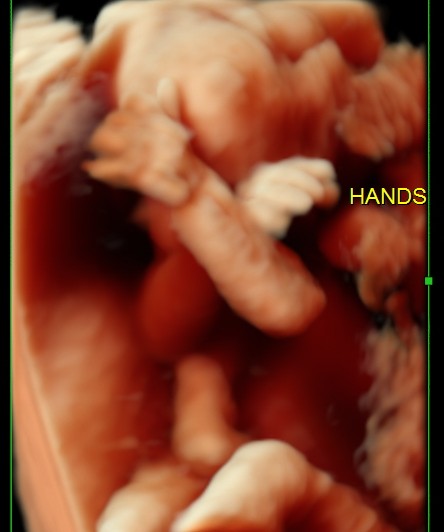

BABY FACE ( Just for fun ) Date: May 25, 2014Author: kriznan Category: 3 d images, fetal face, Fetal Ultrasound, ultrasound images Tags: baby face 3 d images, baby sucking finger, baby yawning Post navigation ← HEMANGIOMA OF THE LIVER IUGR OR SKELETAL DYSPLASIA OR RENAL DYSPLASIA → This is just an intermediate filler . enjoy the expressions. Thinking Yawning or just putting out the tongue Sucking the fingers Wondering So , what is lost now ? ok Papparazi ! enough for the day . go away. Share this: Share on X (Opens in new window) X Share on Facebook (Opens in new window) Facebook Email a link to a friend (Opens in new window) Email Share on LinkedIn (Opens in new window) LinkedIn Share on WhatsApp (Opens in new window) WhatsApp More Print (Opens in new window) Print Share on Reddit (Opens in new window) Reddit Share on Tumblr (Opens in new window) Tumblr Share on Pinterest (Opens in new window) Pinterest Share on Telegram (Opens in new window) Telegram Like Loading...